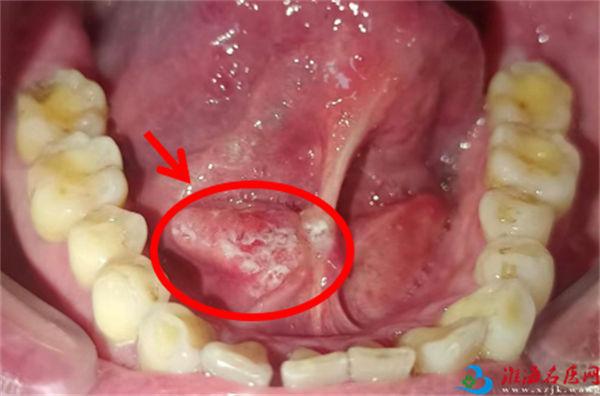

半年前,这位患者注意到舌头下方的口底部位长了一个溃疡,起初并未引起太多的关注。然而,随着时间的推移,溃疡逐渐扩大。由于自服消炎药和涂抹外用药一直解决不了问题,患者最终来到了徐州市口腔医院的口腔颌面外科门诊寻求诊治。

司亚萌主任医师在见到患者口内病灶时立刻察觉到,患者口内的溃疡很有可能已经发展成了癌,于是立刻将患者收治入院。在入院后的进一步检查中,我们发现他的病情比预期更加严重。尽管病程只有半年,溃疡不仅发展成了癌,而且癌细胞可能已经转移至颈深部的淋巴结。这个消息让患者及其家属陷入了巨大的恐慌和困惑之中。